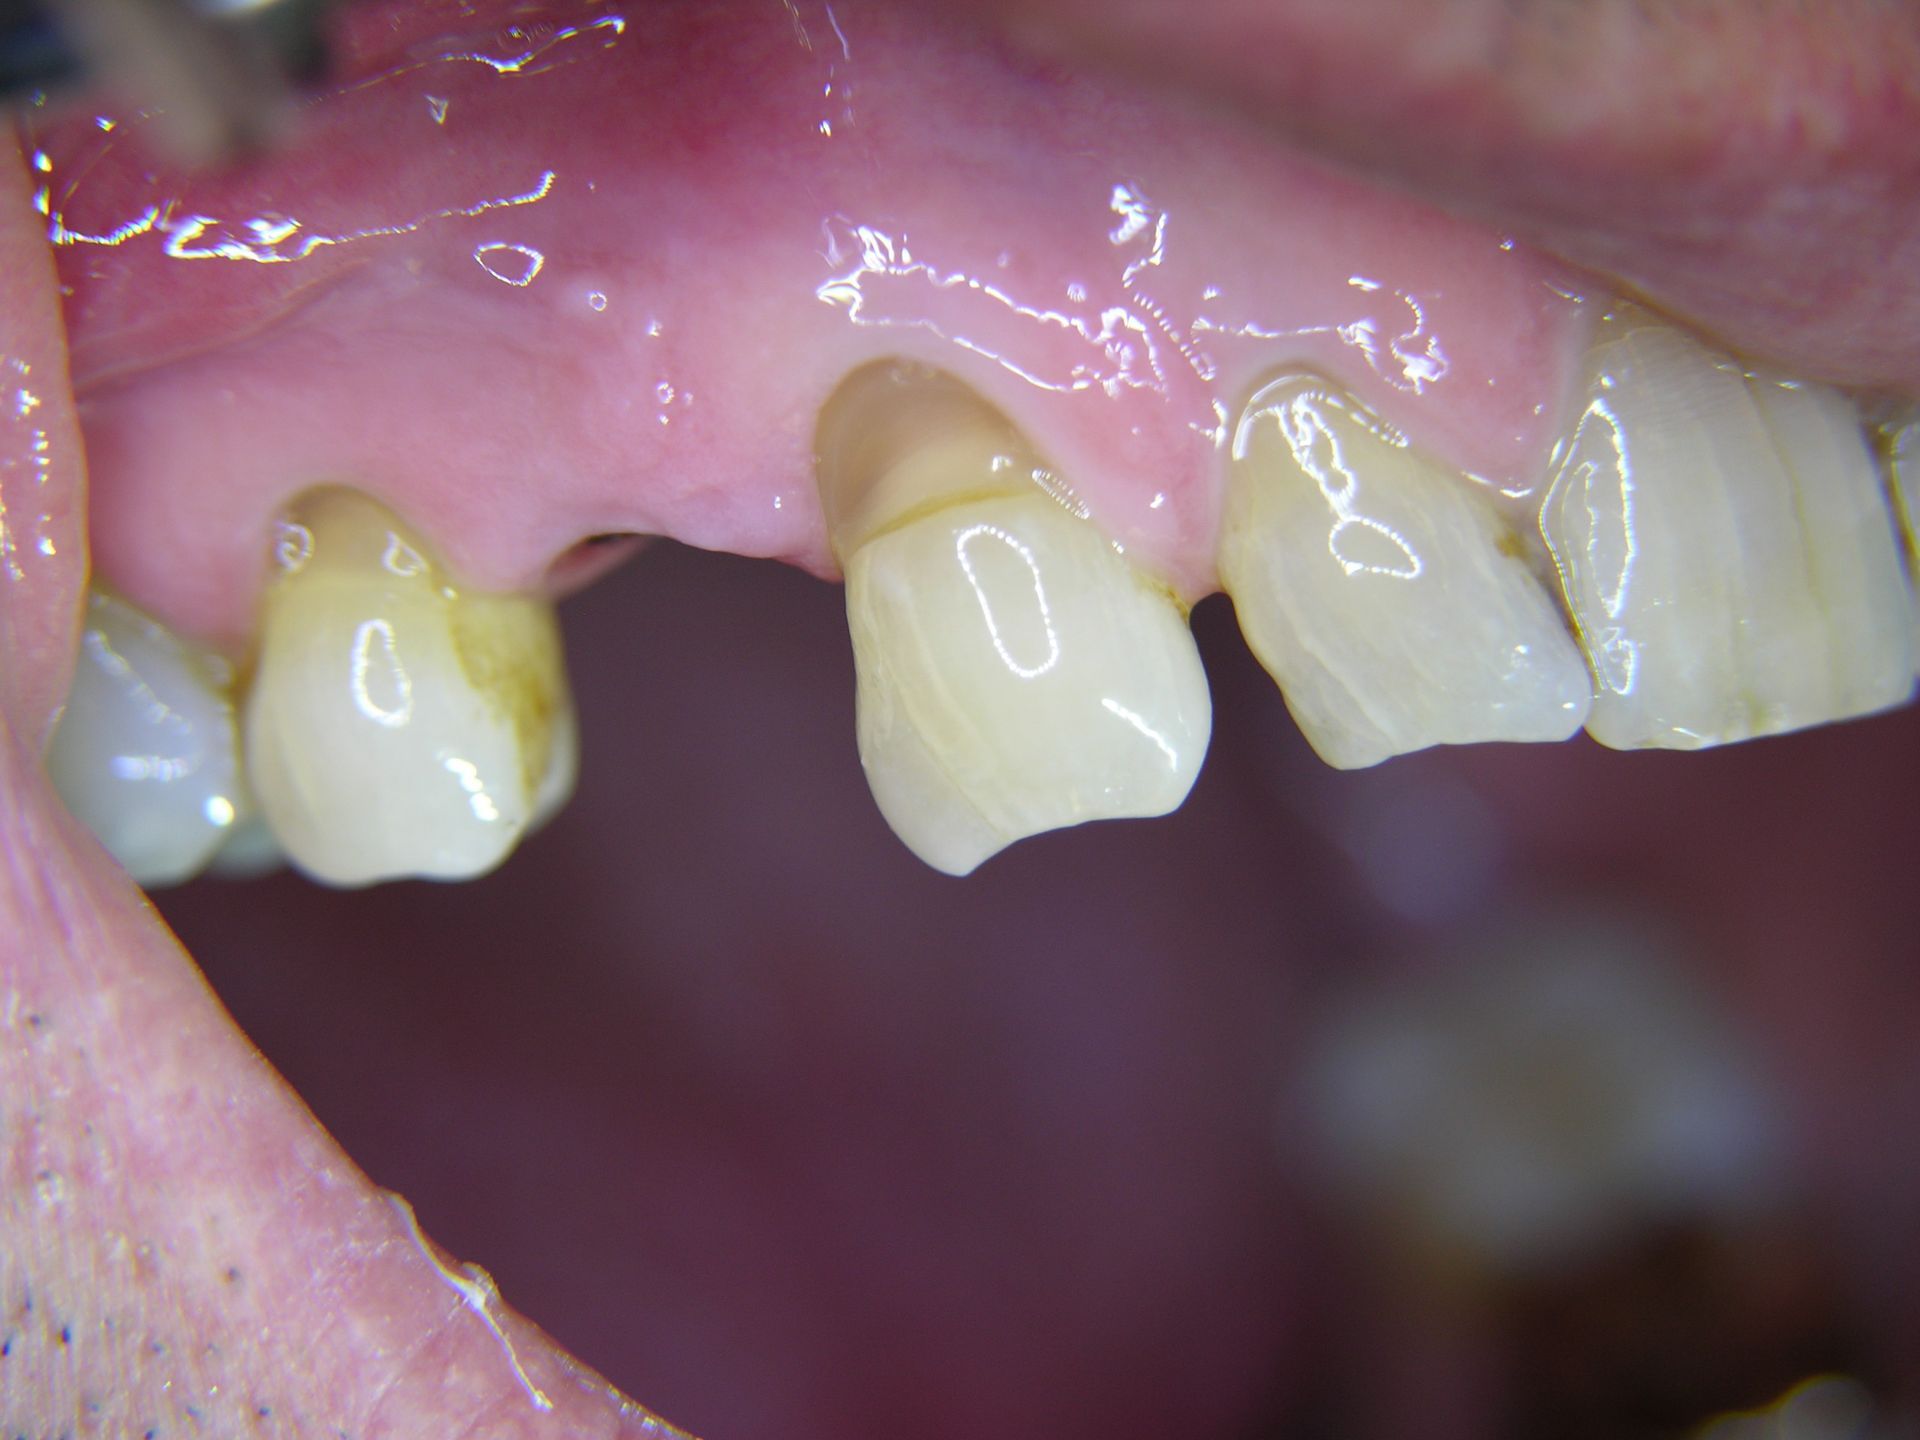

Beispiele von Versorgungen